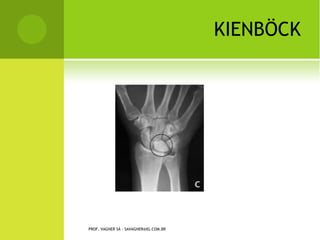

K IENBÖCK

PROF. VAGNER SÁ - SAVAGNER@IG.COM.BR

OSTEOCONDROSES

       Kienbock